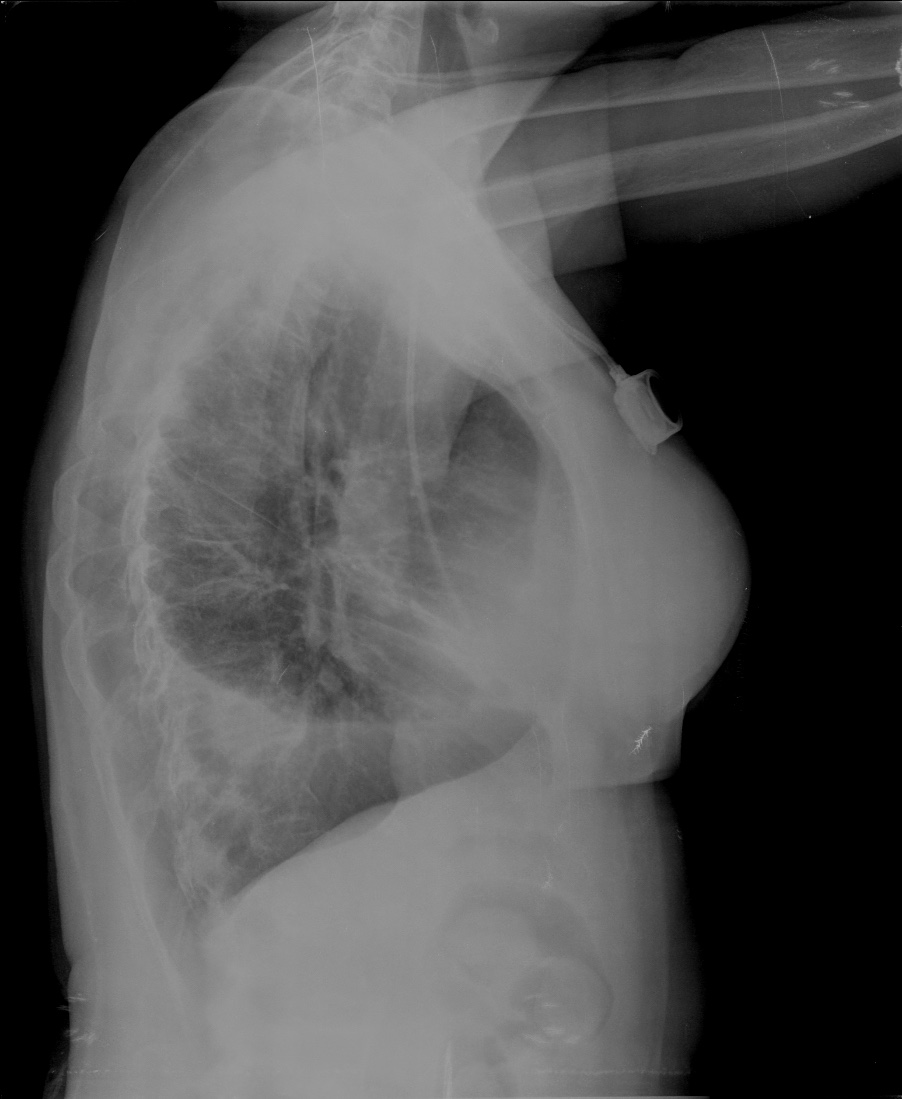

CASO: Febrícula y tos de 4 días de evolución.

Hallazgos:

- En la placa PA se observa una asimetría en los hilios pulmonares, el hilio izquierdo tiene una densidad aumentada.

- Tras examinar la placa lateral se observa un aumento de densidad en la columna que puede ser compatible con una condensación, es el signo de la desnificación vertebral.

SIGNO DE LA DENSIFICACIÓN VERTEBRAL: En la radiografía lateral normal, la densidad de la columna torácica tiende a disminuir desde la parte superior hasta el diafragma; la alteración de ese patrón por la presencia de una densidad superpuesta a la columna, indica la existencia de una consolidación pulmonar. Este signo adquiere especial valor cuando en la proyección posteroanterior la consolidación está oculta en el espacio retrocardíaco o en la base pulmonar.